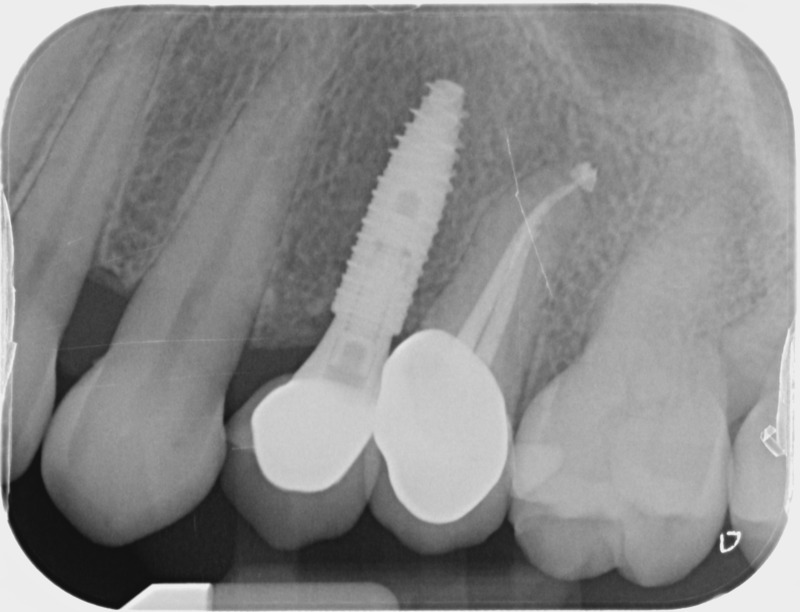

• Couronnes sur implants : Lorsqu’un implant est posé en remplacement des racines d’une dent, il est conçu pour recevoir d’abord un pilier vissé puis une couronne céramique. Le couple couronne - implant se substitue à la dent manquante pour en assurer les mêmes fonctions. Nous pouvons également adapter un bridge sur plusieurs implants dans le cas d’un édentement plus important.

Avant